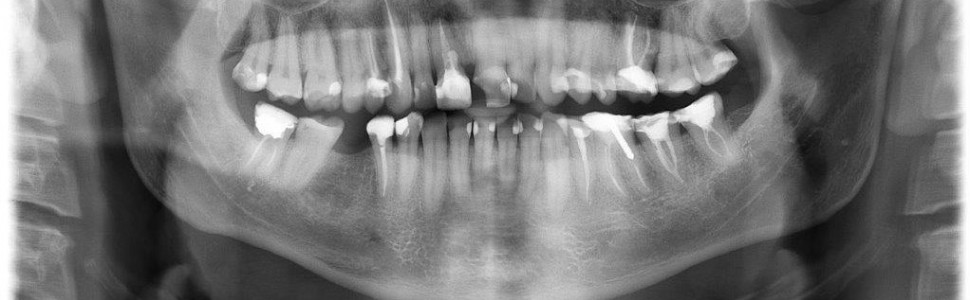

Codzienne przypadki krakowskiego endomaniaka. Kompleksowe leczenie endodontyczne, czyli jak poradzić sobie w trudnych sytuacjach klinicznych i nie zwariować!

Od leczenia pierwotnego po zarządzanie powikłaniami: odseparowane narzędzia, niestandardowa anatomia, zastosowanie CBCT i biomateriałów

W artykule przedstawiono kompleksowe podejście do leczenia endodontycznego pacjenta. Opisano przypadki zarówno leczenia pierwotnego, jak i zarządzania trudnymi przypadkami z zastosowaniem biomateriałów oraz usuwaniem odseparowanych narzędzi.